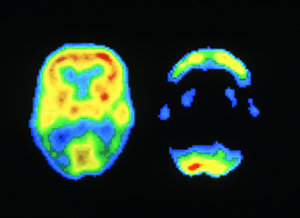

正常大脑(左)和阿尔茨海默病患者的大脑(右)在PET成像时的对比。

在PET成像时,受试者会摄入或被注入痕量放射性材料,以此产生关于新陈代谢、内循环或其他细胞级活动的三维图像。这项研究的共同作者、旧金山分校的放射科医生孙载皓(Jae Ho Sohn)说,人工智能非常适合用于PET,因为在阿尔茨海默病造成神经组织退化前数年,大脑的新陈代谢就已经发生了细微的变化,而神经科医生很难发现这些变化。